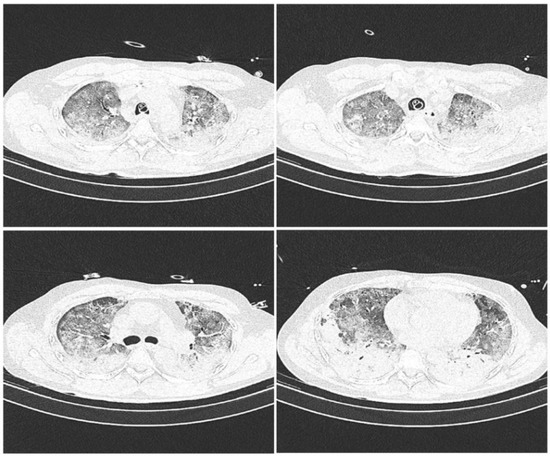

2. Materials and Methods

2.2. Methods